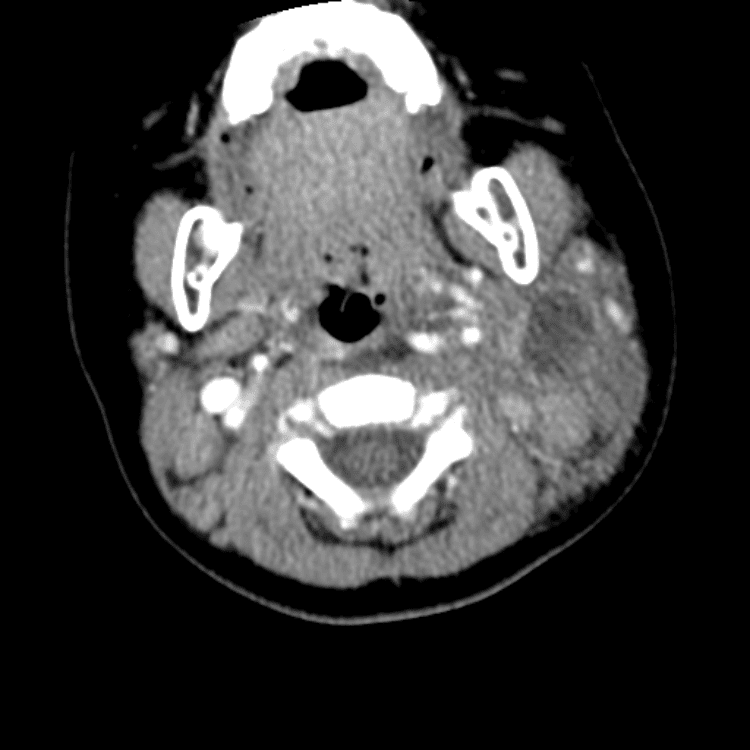

Head and Neck

Practice

Simulates call by including subtle or difficult cases and some normals.

27 cases